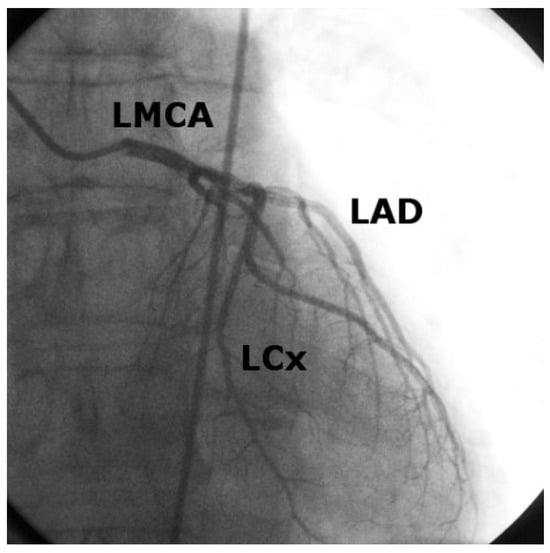

Iatrogenic Left Main Stem Stenosis After Surgical Aortic Valve Replacement

by Jens Robert, David Tüller and Stephan Windecker

Cardiovasc. Med. 2011, 14(3), 101; https://doi.org/10.4414/cvm.2011.01578 - 23 Mar 2011

Surgical aortic valve replacement (SAVR) represents the gold standard in the treatment of symptomatic severe aortic valve stenosis as reflected by the class I indication assigned in the ACC/AHA and ESC guidelines. SAVR effectively relieves symptoms, improves quality of life as well as [...] Read more.

Surgical aortic valve replacement (SAVR) represents the gold standard in the treatment of symptomatic severe aortic valve stenosis as reflected by the class I indication assigned in the ACC/AHA and ESC guidelines. SAVR effectively relieves symptoms, improves quality of life as well as prognosis of affected patients. As with any therapeutic intervention, SAVR is associated with some short and long term adverse events including death, stroke, myocardial infarction, renal failure, bleeding, as well as structural and non-structural valve deterioration. We present two cases of iatrogenic left main stemstenosis within less than one year after SAVR, describe the management and discuss the literature. Full article